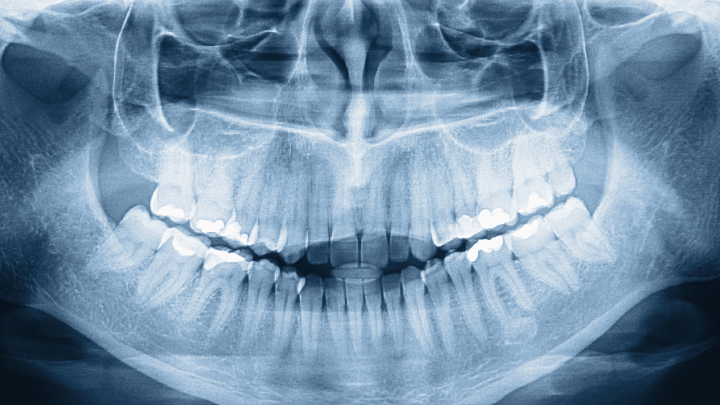

Dentin Hypersensitivity Relief: A Systematic Review and Meta-Analysis

LLLT for sensitive teeth? This review analyzes if low-level laser...